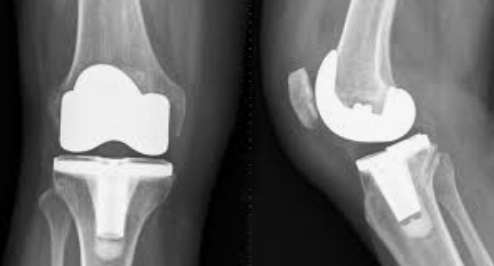

Knee Replacement

Total Knee Replacement

Dr. Nitin Srivastava Dr. Nitin Srivastava is amongst the best doctors in Indrapuram, Ghaziabad who is specialized in Orthopaedics, Joint R...